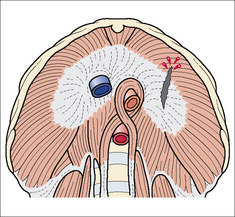

Figure 32.16 The diaphragm viewed from below. Sagittal rupture through the central tendon and muscular part of the left dome from an antero-posterior compressive force. The tendon has a relatively poor blood supply and when ruptured it heals slowly and less effectively than the surrounding muscle.